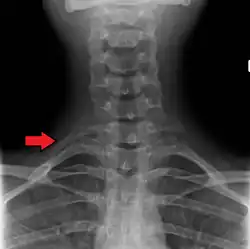

Variación

El número de costillas puede variar. Una de cada 200-500 personas tienen una costilla cervical adicional, siendo un caso predominante en las mujeres.[13] Las costillas supernumerarias intratorácicas son poco usuales.[14] En ocasiones, la costilla remanente de la 7ª vértebra cervical de uno o ambos lados se sustituye por una costilla adicional libre, denominada costilla cervical, la cual puede interferir de forma mecánica con los nervios (plexo braquial) conectados al brazo.

En 1543, el anatomista flamenco Vesalius notó el número de costillas, 24 (12 pares), en su obra clave de anatomía De humani corporis fabrica, lo cual desató una ola de controversia. Debido a la historia bíblica de Adán y Eva, se solía asumir que los hombres tenían menos costillas que las mujeres.[18][19] Sin embargo, solo el 1% de personas tiene la decimotercera o “costilla cervical”,[12] siendo más común de ocurrir en las mujeres que en los hombres.[13]